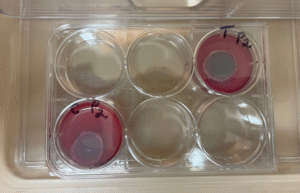

Treatment of the Petri plates inoculated with live bacteria using Ocu-Vet UV-C for 15 seconds at a 10 mm distance.

Photos of the Petri plates, 72 hours after bacterial (Pseudomonas aeruginosa) inoculation.

Image (B) is the control plate. The blue lines divide the plate into quadrants.

Photos of the Petri plates, 72 hours after bacterial inoculation. Both plates show complete (positive) bacterial growth inhibition (full translucency) at the treatment site after two UV-C doses of 15 seconds at a 15 mm distance. The blue lines divide the plate into quadrants.